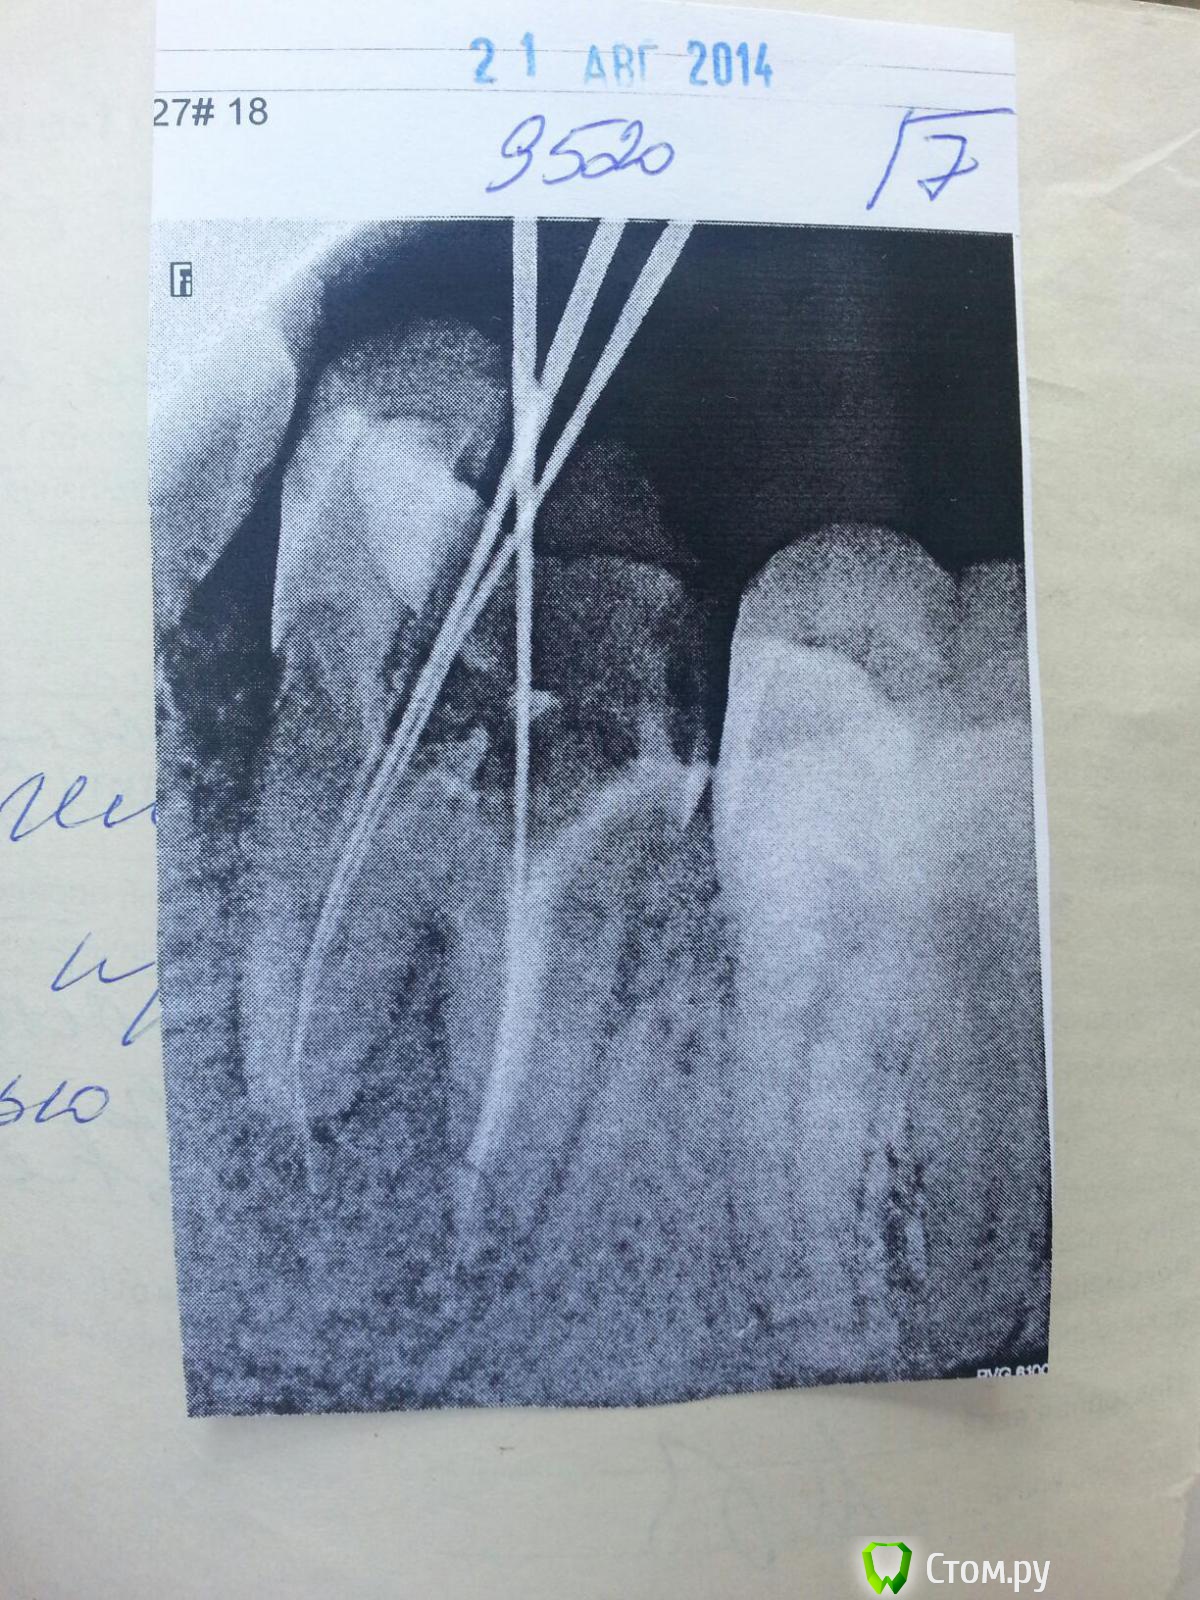

Oleg_90 Опубликовано 23 сентября, 2014 Автор Поделиться Опубликовано 23 сентября, 2014 1-й снимок сделан 31.01.14, когда первый раз пломбировали2-й - 21.08.14 чистили каналы3-й - сегодня Ссылка на комментарий